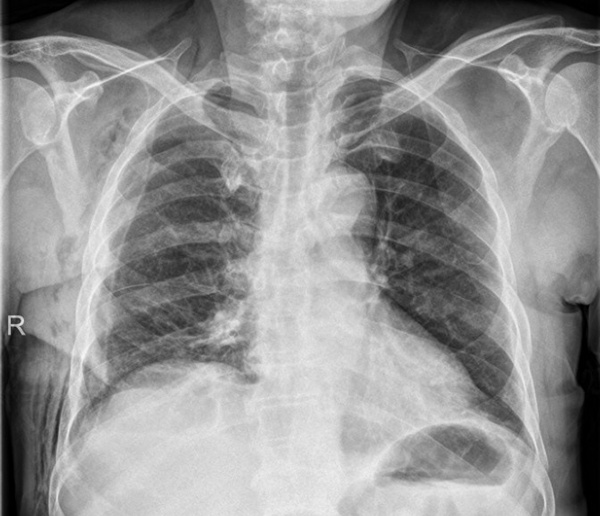

张先生,现年64岁,于常规体检时发现纵隔区有异常肿块,随即被紧急送往医院进行详细检查。通过强化CT扫描,医者发现其前纵隔区域内存在一个直径大约为10厘米乘以8厘米的巨大肿块。此肿物不仅对心包、上腔静脉、左无名静脉等关键生理结构施加了压迫,同时也对其生命安全构成了极大的威胁。稍有不当,便可能引发致命的并发症。

该肿瘤不仅体积较大,而且其位置十分特别,已被归类于2022年世界卫生组织最新确定的罕见肿瘤类型。因此,手术的难度和可能存在的风险都有所上升。为确保手术顺利进行,医院迅速组织了一个由心胸外科、放射科、病理科和麻醉科等多学科专家组成的团队,他们共同进行了联合会诊,并基于CT影像资料进行了多次细致的讨论。